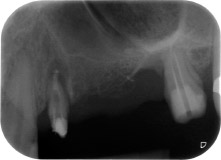

апикално-периодонтална лезия на зъб 24

Фиг. 1: 58-годишна пациентка. Предоперативната рентгенография показва апикално-периодонтална лезия на зъб 24 и хоризонтална загуба на алвеоларна кост във втори квадрант.

58-годишна пациентка се оплаква от болка и повишена подвижност в нейния мост върху зъб 24 с функция на абатмънт. На лице е периодонтално възпаление с дълбочина на джоба 7 mm мезиобукално и повече от 12 mm дистално, както и включена 3 градусова фуркация. Освен това, рентгенографията показва обширна периодонтална лезия около апикалната зона на (друго място) предварително ендодонтски обработен зъб 24 (Фиг. 1).

Една година по-късно, зъби 25 и 26 са екстрахирани в следствие на травма и поради ендо-перио причини, преди поставянето на моста. Комбинирана ендо-перио лезия е диагностицирана за зъб 24 от неясна етиология. Пациентката иска да задържи нейния мост с абатмънт на зъби 24 и 27 и не приема окончателна, подвижна протеза. По този начин, взаимно решихме да положим всички усилия да запазим и двата зъба, въпреки лошата прогноза за тях, която е базирана на рентгенографски и клинични резултати.

Поставянето на два импланта е планирано на места 25 и 26, в хирургична сесия с отворено периодонтално отстраняване и апикоектомия на зъб 24. В следствие на вертикален дефицит на кост в бъдещото имплантно ложе, планирана е вътрешна аугментация на синус.